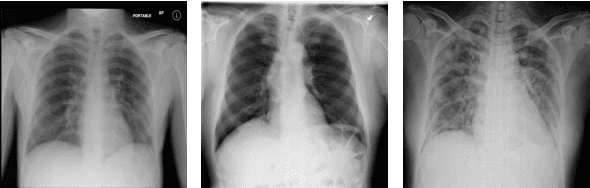

Abstract:The COVID-19 disease was first discovered in Wuhan, China, and spread quickly worldwide. After the COVID-19 pandemic, many researchers have begun to identify a way to diagnose the COVID-19 using chest X-ray images. The early diagnosis of this disease can significantly impact the treatment process. In this article, we propose a new technique that is faster and more accurate than the other methods reported in the literature. The proposed method uses a combination of DenseNet169 and MobileNet Deep Neural Networks to extract the features of the patient's X-ray images. Using the univariate feature selection algorithm, we refined the features for the most important ones. Then we applied the selected features as input to the LightGBM (Light Gradient Boosting Machine) algorithm for classification. To assess the effectiveness of the proposed method, the ChestX-ray8 dataset, which includes 1125 X-ray images of the patient's chest, was used. The proposed method achieved 98.54% and 91.11% accuracies in the two-class (COVID-19, Healthy) and multi-class (COVID-19, Healthy, Pneumonia) classification problems, respectively. It is worth mentioning that we have used Gradient-weighted Class Activation Mapping (Grad-CAM) for further analysis.

Abstract:The Coronavirus was detected in Wuhan, China in late 2019 and then led to a pandemic with a rapid worldwide outbreak. The number of infected people has been swiftly increasing since then. Therefore, in this study, an attempt was made to propose a new and efficient method for automatic diagnosis of Corona disease from X-ray images using Deep Neural Networks (DNNs). In the proposed method, the DensNet169 was used to extract the features of the patients' Chest X-Ray (CXR) images. The extracted features were given to a feature selection algorithm (i.e., ANOVA) to select a number of them. Finally, the selected features were classified by LightGBM algorithm. The proposed approach was evaluated on the ChestX-ray8 dataset and reached 99.20% and 94.22% accuracies in the two-class (i.e., COVID-19 and No-findings) and multi-class (i.e., COVID-19, Pneumonia, and No-findings) classification problems, respectively.

Abstract:The new coronavirus (known as COVID-19) was first identified in Wuhan and quickly spread worldwide, wreaking havoc on the economy and people's everyday lives. Fever, cough, sore throat, headache, exhaustion, muscular aches, and difficulty breathing are all typical symptoms of COVID-19. A reliable detection technique is needed to identify affected individuals and care for them in the early stages of COVID-19 and reduce the virus's transmission. The most accessible method for COVID-19 identification is RT-PCR; however, due to its time commitment and false-negative results, alternative options must be sought. Indeed, compared to RT-PCR, chest CT scans and chest X-ray images provide superior results. Because of the scarcity and high cost of CT scan equipment, X-ray images are preferable for screening. In this paper, a pre-trained network, DenseNet169, was employed to extract features from X-ray images. Features were chosen by a feature selection method (ANOVA) to reduce computations and time complexity while overcoming the curse of dimensionality to improve predictive accuracy. Finally, selected features were classified by XGBoost. The ChestX-ray8 dataset, which was employed to train and evaluate the proposed method. This method reached 98.72% accuracy for two-class classification (COVID-19, healthy) and 92% accuracy for three-class classification (COVID-19, healthy, pneumonia).

Abstract:In late 2019 and after COVID-19 pandemic in the world, many researchers and scholars have tried to provide methods for detection of COVID-19 cases. Accordingly, this study focused on identifying COVID-19 cases from chest X-ray images. In this paper, a novel approach to diagnosing coronavirus disease from X-ray images was proposed. In the proposed method, DenseNet169 deep neural network was used to extract the features of X-ray images taken from the patients' chest and the extracted features were then given as input to the Extreme Gradient Boosting (XGBoost) algorithm so that it could perform the classification task. Evaluation of the proposed approach and its comparison with the methods presented in recent years revealed that the proposed method was more accurate and faster than the existing ones and had an acceptable performance in detection of COVID-19 cases from X-ray images.